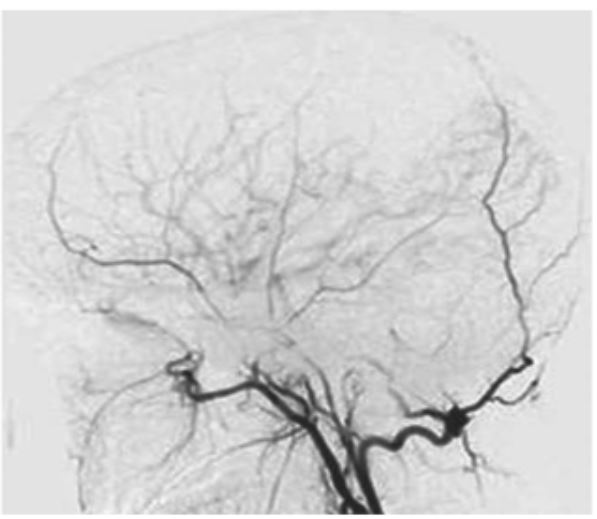

- 우리 뇌의 바닥 쪽에 있는 뇌혈관 중 내경동맥의 끝부분과 이와 연결된 대뇌동맥고리(월리스 동맥륜)가 안쪽부터 두꺼워지면서 혈관이 막히면서 이런 혈관을 대신하기 위해 가느다란 혈관들이 생겨나는 희귀병을 얘기합니다.

- 1960년대 일본에서 뇌혈관 조영술을 연구하다 발견해 혈관 모양이 연기가 모락모락 올라가는 것처럼 보인다고 하여 모야모야병이 이라고 이름을 붙였습니다.

- 혈액 공급을 위해 생긴 작은 혈관들은 다시 막힐 가능성이 높아 문제가 되며, 10세 전후 연령의 아이들에게 많이 발견되어 어린이 뇌졸중이나 소아 뇌졸중으로 불리기도 하는 희귀 질병입니다.